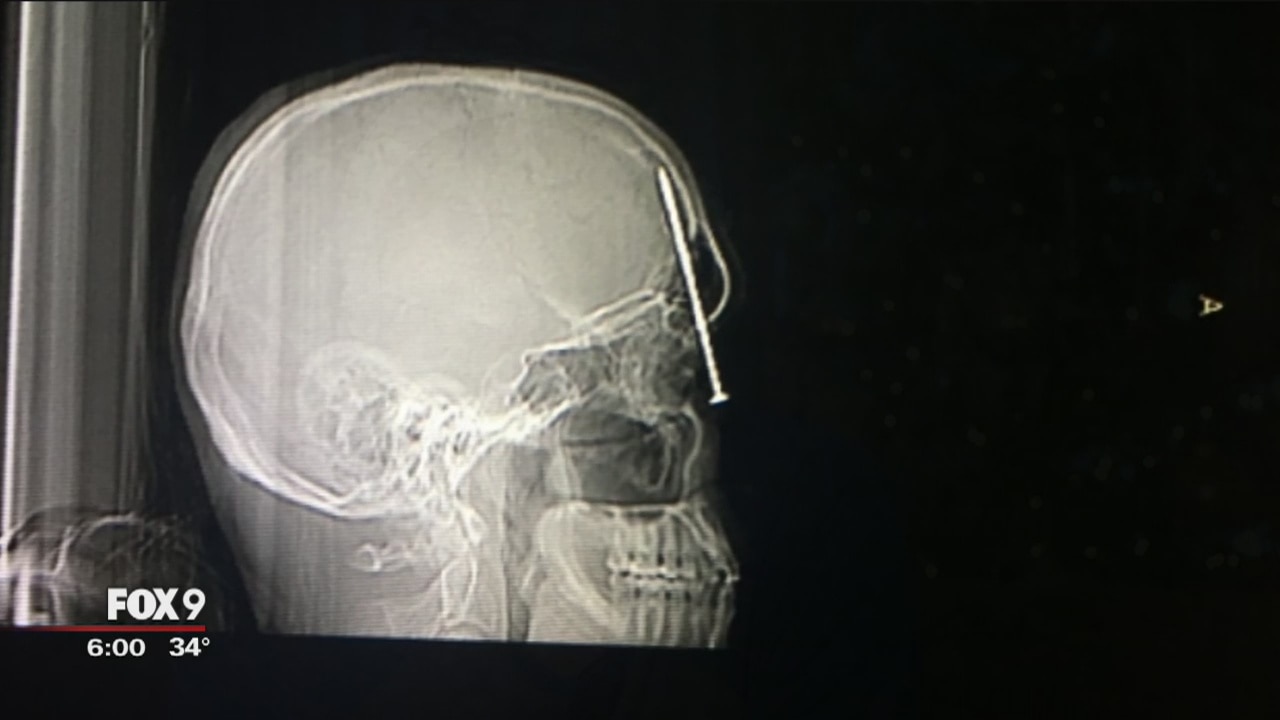

He's perhaps the luckiest and, unluckiest man in the world. A Stillwater homebuilder missed death by just millimeters after a nail from a nail gun ricocheted, and sent a spike right into his head.